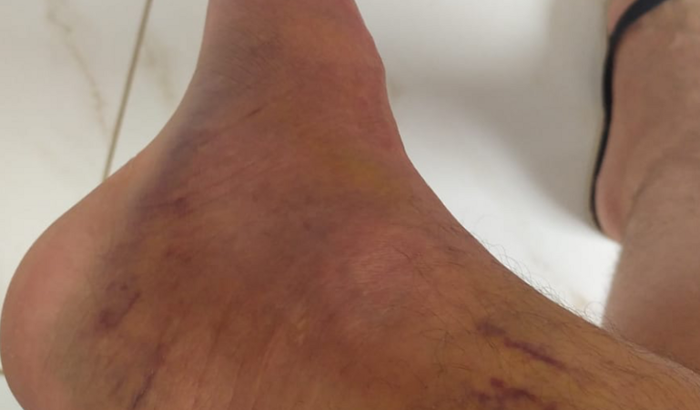

Me chamo Ythalo, tenho 25 anos, há quase um ano no dia 26/02/2022 sofri uma fratura no tornozelo do pé direito, no início pensei que não fosse nada grave, mas ao consultar me informaram que tinha um pequeno derrame articular e houve uma fratura lateral do corpo do tálus. Tive um repouso de 60 dias, e houve um pouco de alívio da dor, voltei as atividades normais, mas ao passar do tempo a dor voltou e foi aumentando cada vez mais. Fiz uma nova consulta e o médico me informou que devo fazer a cirurgia. Hoje me encontro sem trabalhar a 02 meses por não conseguir por causa da dor, e na fila do sus para a cirurgia a 05 meses, mas pelo fato de ainda não terem me chamado para a cirurgia decidi criar a Vakinha para fazer ela o mais rápido no particular, a cirurgia custa 6.000,00 e vou ter que fazer uma nova tomografia e uma nova consulta que vão ficar no valor de 1.000,00. Preciso voltar a trabalhar e voltar as minhas atividades normais, mas isso só será possível após essa cirurgia. Conto com sua ajuda e serei muito grato.